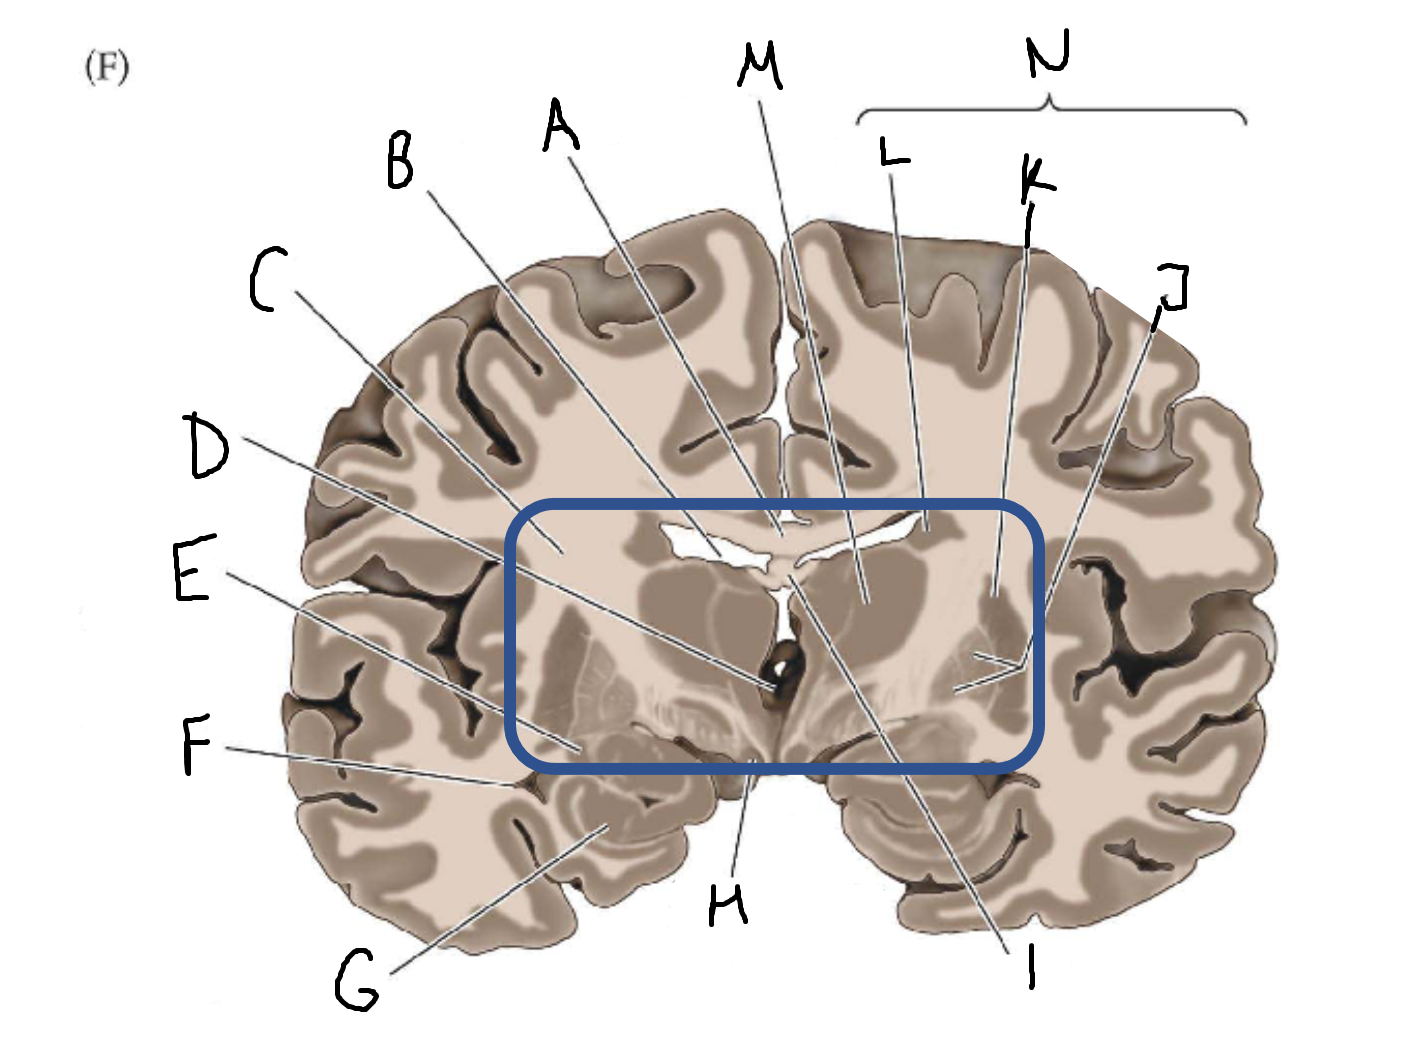

A

corpus callosum

B

lateral ventricle

C

internal capsule

D

third ventricle

E

tail of caudate nucleus

F

lateral ventricle

G

hippocampus

H

mammillary body

I

fornix

J

globus pallidus

K

putamen

L

caudate

M

thalamus

N

basal ganglia